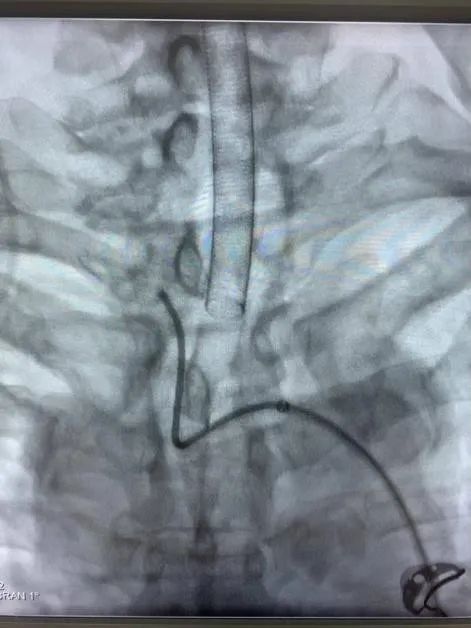

近日,省人民医院神经外科为一位高龄动脉瘤患者施行了介入治疗,成功栓塞了破裂的大脑中动脉瘤。患者因突发晕厥后头痛不适入院,急诊行颅脑CT检查提示蛛网膜下腔出血,行颅脑CTA检查后证实患者存在右侧大脑中动脉瘤。患者高龄,既往基础病多,高血压病、糖尿病、冠心病、双侧颈动脉硬化、双侧腹股沟疝术后等,手术风险较大,经家属签字同意后,当日急诊全麻下行“右侧大脑中动脉瘤介入栓塞术”,术中见血管迂曲明显,导管到位艰难,经过努力,手术顺利结束。术后予多次腰椎穿刺术释放血性脑脊液,患者头痛头晕症状渐缓解。患者住院治疗10天后顺利康复出院,未留后遗症。

动脉瘤主要有两种治疗方式:开颅手术和介入栓塞。两种方法比较,介入栓塞手术时间短、康复快、不需开颅、可同时治疗多个动脉瘤,适合高龄、分级高的患者,其中血管内弹簧圈栓塞术是颅内动脉瘤最常见的一种介入治疗方式,随着介入新材料、技术的不断进步,介入栓塞的优势日渐明显。